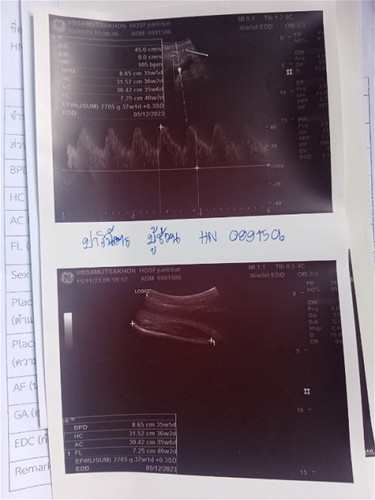

อันนี้คือซาวอะไรหรอคะ รู้แค่ว่าอีกอันซาวด์ลูกในท้องและขออนุญาตดูเพศให้หน่อยค่ะ🥺🥺

รูปบนวัดการเต้นของหัวใจ ล่างกระดูกต้นขาค่ะ

หมอวัดขนาดต่างๆคะ

ขอบคุนค่ะ อีกไม่กี่สัปดาห์ก็จะคลอดแล้ว